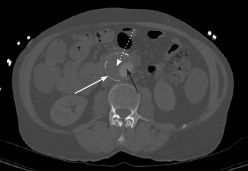

Ultrasound is the modality of choice for detection and screening; however, computed tomography (CT) angiography of the abdomen is helpful to better characterize the anatomical location and aneurysm characteristics, predict prognosis, and can aid in surgical planning. (See Figures 1 and 2.) Understanding the exact location of the aneurysm in relationship to the renal arteries and other vascular structures can help with repair approach and feasibility. For example, aneurysms with shorter necks have poorer outcomes. In stable patients, it also can help identify impending rupture and the extent of aortic wall involvement. It should be noted that unstable patients should not be sent to the CT scanner prior to stabilization.18

Figure 1. Computed Tomography Showing Abdominal Aortic Aneurysm with Intramural Thrombus, Transverse Plane View |

White arrow: aortic wall; black arrow: aortic lumen; white dotted arrow: thrombus Source: Image courtesy of J. Stephan Stapczynski, MD. |